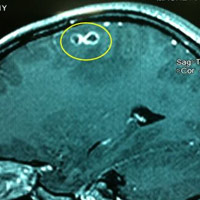

Ảnh minh họa

Người không phải là vật chủ chính nên thông thường, ấu trùng sẽ chết và tạo ra ổ hoại tử, hủy hoại tế bào cơ thể người, đặc biệt tế bào gan. Nếu phát hiện sớm, tổn thương gan nhỏ thì có thể điều trị nội khoa.

Trường hợp gan bị tổn thương lớn, không thể điều trị nội khoa thì mới phải cắt bỏ. Ấu trùng toxocara không thể phát triển thành giun trưởng thành trong cơ thể người và không thể tái lặp chu kỳ sống ở người. Ấu trùng có thể tồn tại trong các tổ chức nhiều năm nếu không được điều trị.

Người mắc giun đũa chó hay bị tổn thương vùng tế bào mà giun đũa di chuyển đến. Các tổn thương ở phổi có thể bị chẩn đoán nhầm với tổn thương ung thư. Các tổn thương ở võng mạc có thể nhầm với u nguyên bào võng mạc.